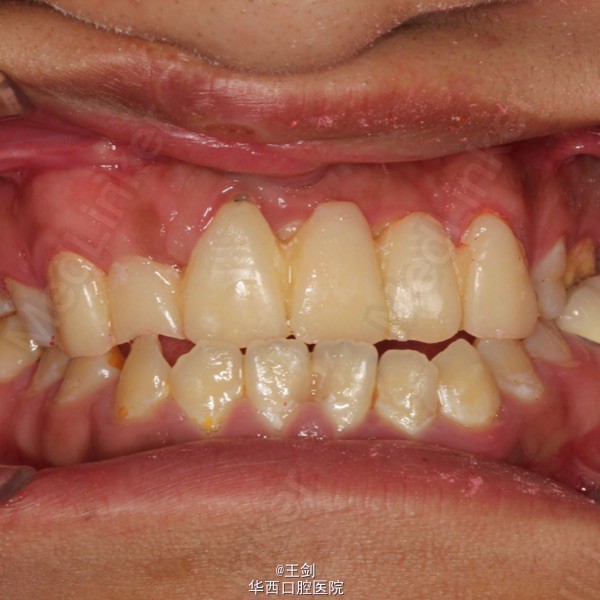

由于11牙正好位于中线,为保证修复效果,11牙作截冠处理,12牙残根纤维桩修复,并将12牙做成11牙的形态,最后做固定桥修复。图中显示牙体预备后正侧面观,可见前牙为反合状态,通过固定桥修复讲前牙关系改为切合。最后一图为戴暂冠后

最终修复效果